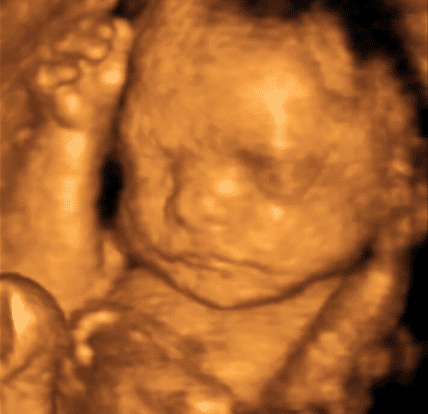

Fetal Development: Week 28

Human fetus age 28 weeks – Stock Image – F015/6737 – Science Photo Library

Human Fetus At Week 28 Of Gestation Photograph by Sebastian Kaulitzki …

Foetus at 28 weeks, artwork – Stock Image – F005/0655 – Science Photo …